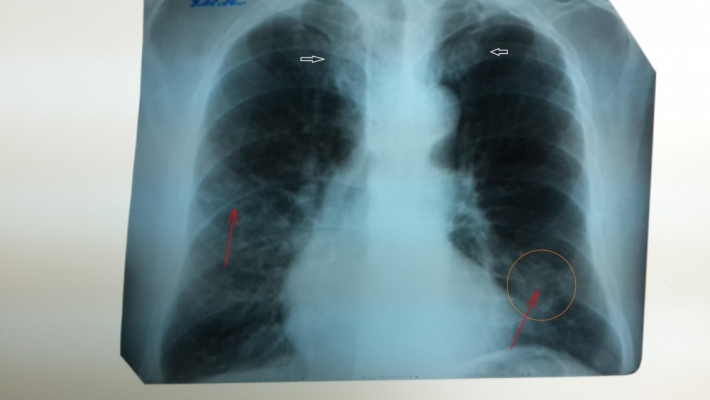

- Со слов женщины, она заболела 30 марта, за медпомощью не обращалась, лечилась самостоятельно. Сегодня (15 апреля - прим. ред.) она почувствовала себя гораздо хуже и обратилась в лечебное учреждение. Она была доставлена бригадой скорой помощи, где в приемном покое больную осмотрели, выполнили рентгенографию грудной клетки. Женщине был поставлен диагноз "двухсторонняя пневмония". После чего женщина потеряла сознание, ей начали оказывать реанимационные мероприятия, но они к успеху не привели, и через 30-35 минут была констатирована смерть больной.